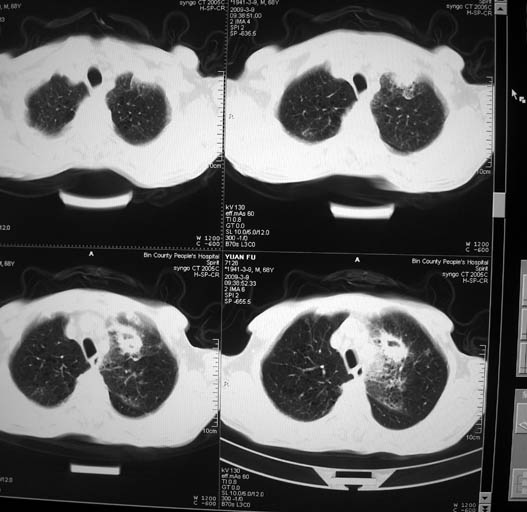

男,68岁,左上肺占位,肺门淋巴结转移?

支持楼主!(左上肺周围性肺癌伴纵隔淋巴结转移)

左上肺周围性肺癌伴纵隔淋巴结转移

1)考虑左肺上叶尖段周围型肺癌并阻塞性肺炎,纵隔淋巴结转移。2)心包少量积液。

支持楼主!(左上肺周围性肺癌并阻塞性肺炎、纵隔淋巴结转移)

考虑左肺上叶尖段周围型肺癌并阻塞性肺炎,纵隔淋巴结转移.

1)考虑左肺上叶尖段周围型肺癌并阻塞性肺炎,纵隔淋巴结转移。2)心包少量积液